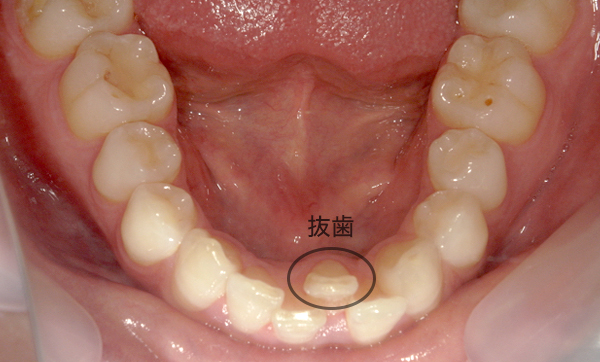

症例_009 「上下の前歯」症例

治療期間:7ヶ月金額:54万円+税20代女性捻転歯一部の反対咬合前歯のガタガタ